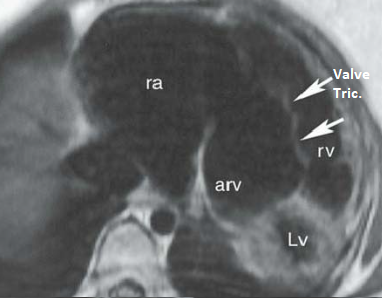

Anomalie d’Ebstein

- Déplacement inférieur de la valve tricuspide

- Dilatation massive de l’OD (signe du carton)

- VD “atrialisé”